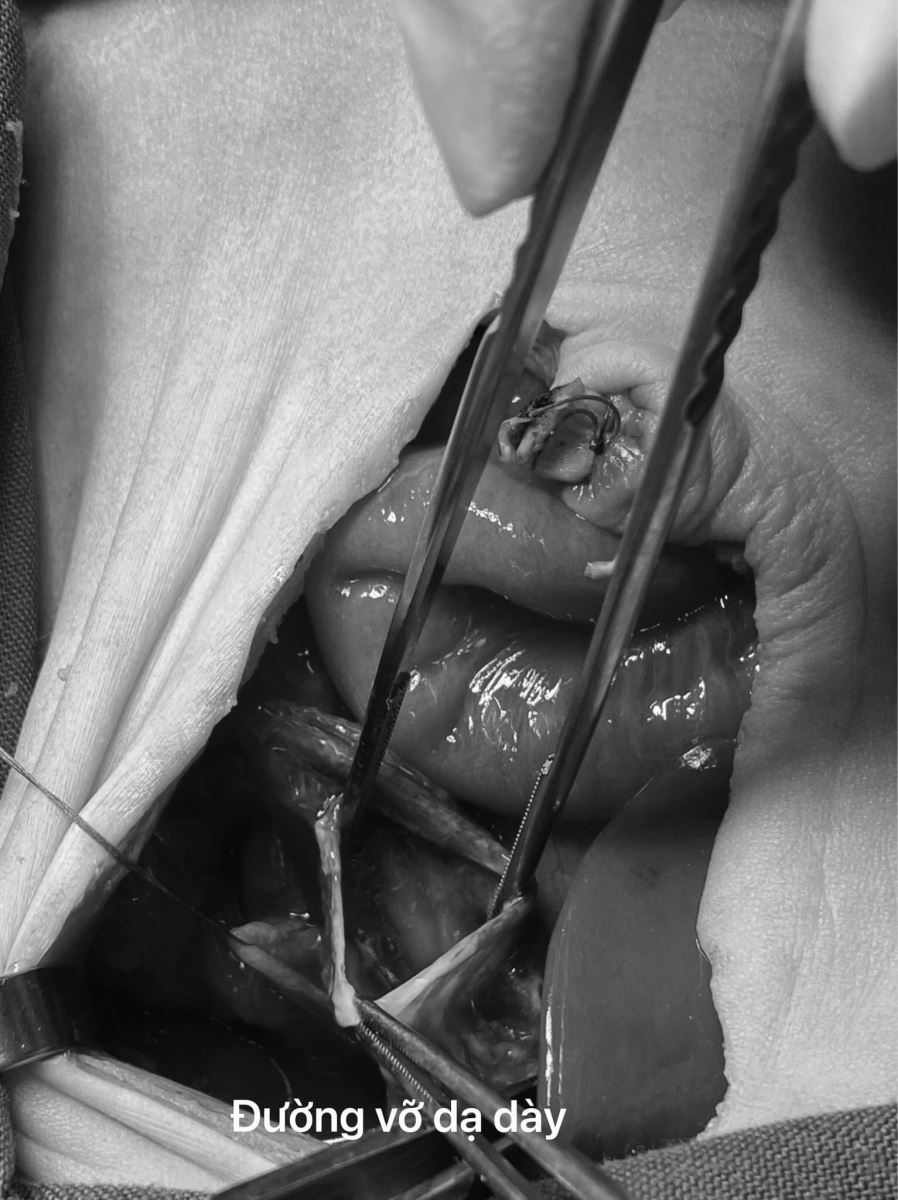

Tiến sĩ, bác sĩ Châu Văn Việt, Trưởng khoa Ngoại Nhi cho biết: Trong quá trình phẫu thuật cấp cứu cho bé, kíp mổ bất ngờ phát hiện dạ dày bé có một lỗ thủng to từ đáy vị đến thân vị. Toàn bộ mặt trước của lỗ thủng không có lớp cơ, chỉ có niêm mạc. Các bác sĩ đã tiến hành cắt lọc và khâu phục hồi dạ dày, kiểm tra lưu thông tá tràng. Ca bệnh là trường hợp hiếm gặp, tỷ lệ tử vong thường chiếm từ 50 - 80%. Tuy nhiên với sự phối hợp tích cực liên khoa cùng những tiến bộ của ngành Ngoại nhi, ca bệnh của bệnh nhi H.T.B nói riêng, những ca bệnh nặng như: sinh non tháng, nhẹ cân, có các dị tật bẩm sinh đã được xử trí kịp thời và điều trị thành công tại Bệnh viện.